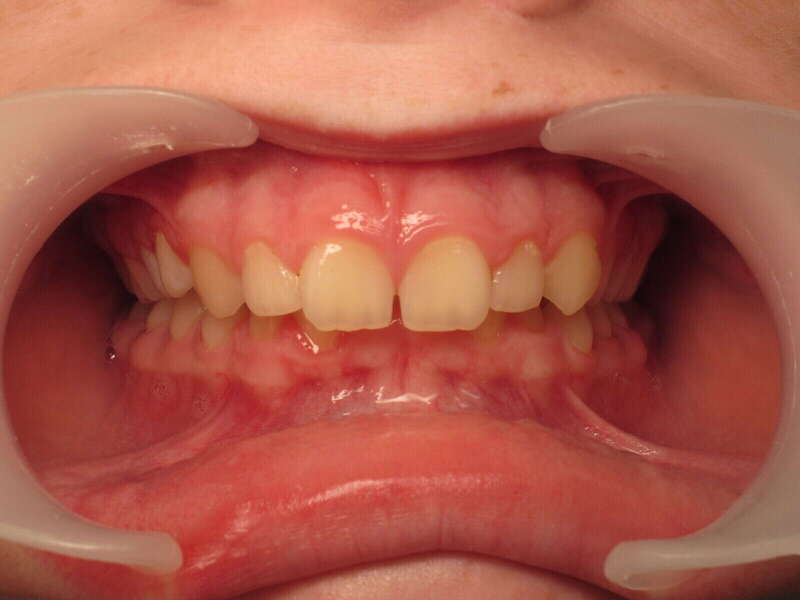

Ce cas d’interception chez un enfant de 8 ans démontre l'efficacité des aligneurs pour corriger des troubles fonctionnels précoces. Le diagnostic présentait des inversions d'articulé provoquant une déviation de la mandibule vers la gauche et un décalage des milieux.

Grâce à une coopération exemplaire et un traitement totalement indolore, l'expansion de l'arcade a permis de recentrer la mâchoire. Cette intervention a littéralement remis la croissance sur les rails, neutralisant le risque d'asymétrie faciale squelettique.

• Correction fonctionnelle : Recentrage immédiat de la mandibule et des milieux inter-incisifs.

• Prévention : Création d'un environnement favorable pour les dents définitives à venir.

• Bien-être : Approche douce respectant le confort de l'enfant.

C'est une étape fondamentale qui simplifie l'avenir orthodontique du patient tout en garantissant un développement facial harmonieux.

Avant